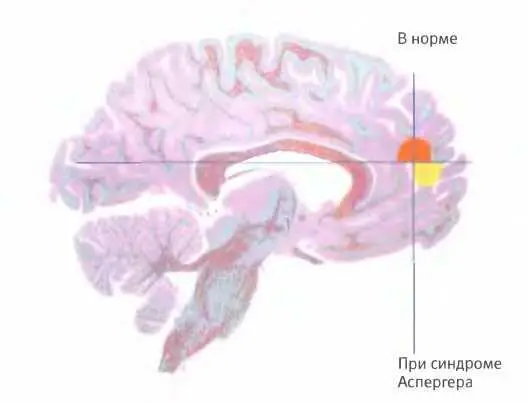

Когда здоровый человек знакомится с текстом, в котором рассказывается о чьем-то психологическом состоянии, у него активируется средняя часть префронтальной коры левого полушария (выделенная область вверху), а когда тот же текст зачитывают пациенту, страдающему синдромом Аспергера, у него активируется другая область, расположенная непосред ственно под первой.

У большинства людей вся эта сложная работа осуществляется бессознательно. По-видимому, только людям, страдающим аутизмом, приходится задействовать в такой работе новую кору (отделы коры больших полушарий, отвечающие за высшие функции мозга). На это указывают результаты описанного ниже исследования, проведенного психологами Утой Фрит и Франческой Аппе совместно с учеными из Отделения когнитивной нейробиологии фонда “Уэллком траст”.

Сканирование мозга показало, что у здоровых испытуемых в поисках ответа на первый и второй вопросы были задействованы разные отделы мозга. Первый вопрос, требовавший оценить психологическое состояние другого человека (в данном случае — ошибочное убеждение вора, что он разоблачен), вызывал активацию определенного участка в середине префронтальной коры — одной из самых эволюционно развитых областей нашего мозга. Когда испытуемые размышляли над ответом на второй вопрос, активации этого участка не наблюдалось.